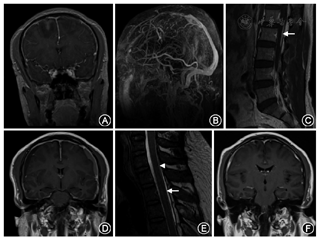

患者男性,43岁,因"直立位头痛2个月余"于2018年7月14日入院。患者2个月余前出现全头部胀痛,程度剧烈时不能忍受,伴恶心、颈部僵硬感,躺下后头痛可立刻缓解,直立后即刻出现头痛,并随直立时间延长而头痛逐渐加重。无畏寒发热,无畏光畏声,无鼻塞脓涕,无视物改变等不适。1个月半前患者从国外乘飞机回国,次日下午出现一过性意识丧失、四肢抽搐,伴双眼上翻、口吐白沫、牙关紧闭、舌咬伤,约5 min后意识逐渐转清,不能回忆发作情况。当地医院头颅CT考虑"蛛网膜下腔出血"。次日患者因肢体抽搐再发且持续不缓解,至上海某医院急诊就诊,查头颅CT提示"双侧额叶及右侧顶叶出血灶",头颅增强MRI提示"双侧额叶出血,硬脑膜广泛强化增厚,上矢状窦血栓形成"(图1A)。头颅磁共振静脉血管成像也确认了上矢状窦血栓形成(图1B)。头颅磁共振动脉血管造影未见明显异常。腰椎穿刺未见脑脊液流出。诊断考虑"自发性低颅压合并颅内静脉窦血栓形成",予卧床、补液、抗凝、抗癫痫治疗。患者意识恢复后发现存在左侧肢体偏瘫。住院期间完善腰椎增强MRI提示"L1~2水平椎管内硬膜外后高信号影,血肿?"(图1C)。治疗后患者头痛好转,直立活动无头痛,左侧肢体无力缓解。出院后继续口服华法林、左乙拉西坦。出院3周后,患者再次出现头顶部隐痛,久立后头痛加重,平卧后头痛可稍缓解,但仍存在,头颅CT提示"双侧硬膜下血肿"。患者转入浙江大学医学院附属邵逸夫医院进一步治疗,入院体检:体温36.7 ℃,脉搏68次/min,呼吸18次/min,血压142/88 mmHg(1 mmHg=0.133 kPa),意识清楚,精神可,定向力完整,口齿清楚,双侧瞳孔等大等圆、直径3 mm,直接、间接对光反射灵敏,眼球活动无特殊,未及眼震,双侧额纹、鼻唇沟对称,口角无歪斜,鼓腮可,伸舌居中,咽反射正常,软腭对称上抬,抬头、转颈、鼓腹有力,肌张力正常,四肢肌力Ⅴ级,双侧指鼻试验、轮替试验、跟膝胫试验正常,双侧深浅感觉正常对称,双侧浅反射正常,双侧腱反射(++),双侧巴宾斯基征阴性,脑膜刺激征阴性。患者既往体健,本次外院住院期间发现糖耐量异常,餐后血糖偏高。否认近期外伤、硬膜外麻醉史。入院后完善颅脑增强MRI提示"右侧额顶部亚急性硬膜下血肿,左侧额颞顶部急性硬膜下血肿,少量蛛网膜下腔出血考虑,脑室较小,硬脑膜明显增厚强化"(图1D)。脊柱水成像示"颈胸交界处可疑脑脊液漏,下颈段及上胸段脊髓背侧硬膜外积液考虑"(图1E)。腰椎穿刺测压3 mmH2O(1 mmH2O=0.009 8 kPa)。入院后予停用抗凝药物,于胸段行2次硬膜外血贴治疗,复查头颅CT示血肿较前吸收,患者直立活动无头痛再发。血贴治疗后1个月门诊复查头颅MRI增强提示颅内血肿较前吸收,硬脑膜强化较前改善(图1F)。现患者随访1年余,无头痛再发。